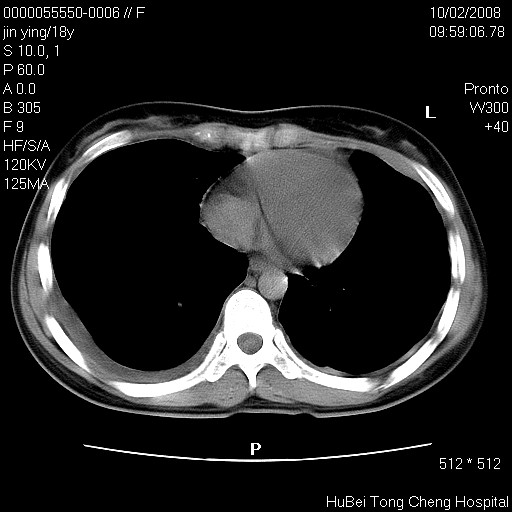

患者 女,18y。发热十余天,伴咳嗽。pe:t39⒈℃,bp 110/80mmhg,p 86次/min。神清,精神欠佳。双肺可闻及少许湿罗音。既往史不详。

临床诊断:肺部感染?

胸部ct轴位平扫(层厚10mm,螺距1.5,重建间隔10mm),图像如下: